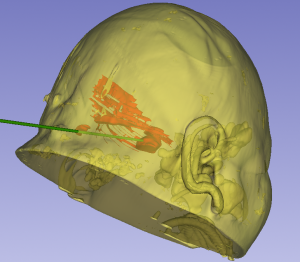

2026年4月29日 Home立体定向技术脑干出血急诊穿刺引流,抢救生命 脑干出血急诊穿刺引流,抢救生命 By admin 立体定向技术 0 Comments 病人1,4月13日急性脑干出血,迅速神志不清 术前CT显示脑干出血 脑干出血发病时 手术计划 术后复查,显示定位准确,穿刺道完全符合术前计划 术后7天,血肿基本引流干净 手术后15天情况 现病人生命体征平稳,正在促醒康复中 About Author admin Add a Comment 取消回复您的邮箱地址不会被公开。 必填项已用 * 标注Comment:*Name:* Email Address:* Website: Save my name, email, and website in this browser for the next time I comment. Δ